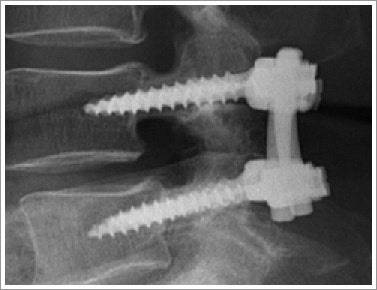

척추고정술은 손상된 척추뼈를 고정하여 척추의 안정성을 확보하는 수술입니다. 척추의 구조적 문제를 교정하고, 통증을 완화하며, 신경 기능을 보호하는 것이 주된 목표입니다. 주로 퇴행성 디스크 질환, 척추측만증, 척추분리증, 외상으로 인한 변형 등에 적용됩니다. 예를 들어, 반복되는 허리 통증으로 일상생활이 어려운 환자나 척추가 비정상적으로 휘어진 청소년에게 척추고정술은 효과적인 치료법이 될 수 있습니다.

4. 고정 장치 설치: 나사, 케이블, 플레이트 등을 사용하여 척추를 고정합니다.